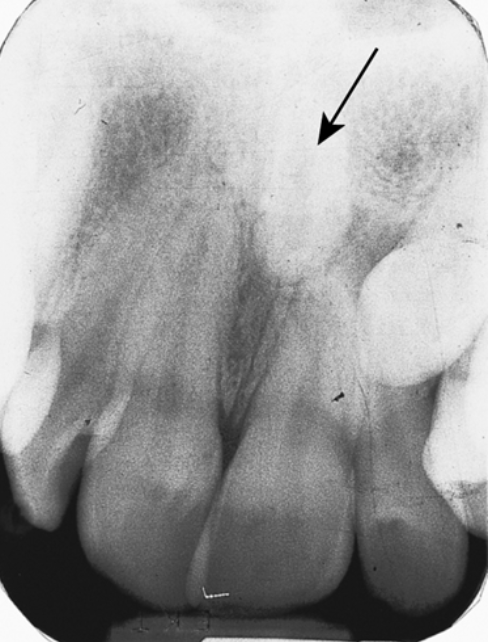

<p>1. After reviewing Fig. 5.23, what term would you use to describe this wear?</p><p>a. Abfraction</p><p>b. Abrasion</p><p>c. Attrition</p><p>d. Erosion</p>

1. After reviewing Fig. 5.23, what term would you use to describe this wear?

d. Erosion

2. Using the Universal Numbering System what tooth numbers are wearing in Fig. 5.23?

a. 8, 9

<p>6. What tooth tissue is seen in Fig. 5.23 that is yellow in color?</p><p>a. Enamel</p><p>b. Dentin</p><p>c. Cementum</p><p>d. Pulp</p>

6. What tooth tissue is seen in Fig. 5.23 that is yellow in color?

b. Dentin

<p>9. Looking at Fig. 5.23, which tooth/teeth looks suspicious on the mesial surface using the International Numbering System?</p><p>a. 1.2</p><p>b. 1.3</p><p>c. 2.3</p><p>d. b. and c.</p>

9. Looking at Fig. 5.23, which tooth/teeth looks suspicious on the mesial surface using the International Numbering System?

a. 1.2

<p>43. What is the term for the extra tooth in Fig. 5.29 pointed out by the arrow?</p><p>a. Mesiodens</p><p>b. Macrodontia</p><p>c. Microdontia</p><p>d. Anodontia</p>

43. What is the term for the extra tooth in Fig. 5.29 pointed out by the arrow?

a. Mesiodens